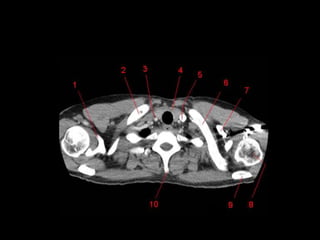

TC mediastino superior